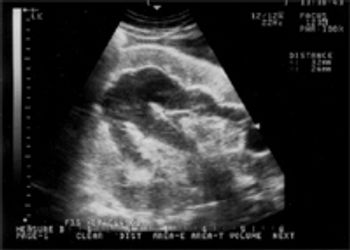

A 5-year-old Oldenburg gelding used for dressage, was presented for evaluation of mild bouts of recurrent colic, more frequent over the past month. The colic signs included flank watching and intermittent sternal recumbency and were either self-limiting or responsive to a single dose of Banamine.